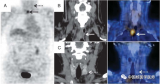

最新研究可能有助于确定PSMA PET/CT在复发性前列腺癌中的作用

根据在荷兰阿姆斯特丹举行的第37届欧洲泌尿学协会大会上的报告,最近的研究结果为根治性前列腺切除术(RP)后生化复发(BCR)前列腺癌患者使用68Ga PSMA PET/CT的最佳时机和适应症提供了线索。 2022-08-06 PET/CT核医学